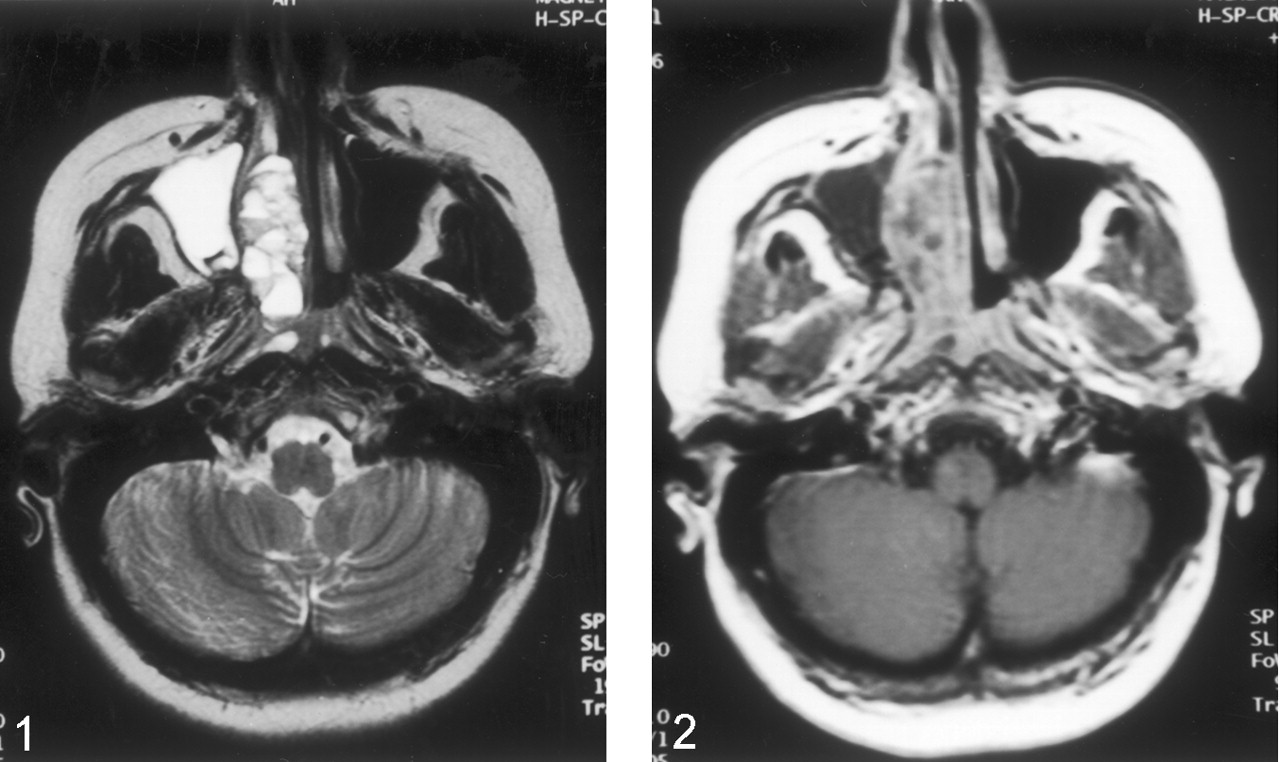

MR examination was performed with a 1.5-T MR unit (Magnetom Vision; Siemens Medical Systems, Erlangen, Germany). T1-weighted spin-echo images (TR/TE, 635/14) and T2-weighted turbo spin-echo images (5000/99) were obtained in the coronal and axial planes (Fig 1). A lobulated mass involving the right nasal cavity and ethmoid sinus extended toward the right maxillary sinus laterally and to the periorbital area superolaterally. The mass caused compression of the right optic nerve and extended to the right torus tubarius posteriorly. The lesion also extended into the anterior cranial fossa. On T1-weighted images, the mass was isointense to hyperintense relative to the neighboring skeletal muscles. On T2-weighted images, the lesion was mainly hyperintense, with fluid-fluid levels in its nasal component. After the administration of IV contrast material (Gadolinium dimeglumine, 0.1 mmol/kg), the periphery and septa of the lesions were enhancing (Fig 2).

Transverse T2-weighted MR image demonstrates the lesion in the right side of nasal cavity and fluid-fluid levels within the lesion.